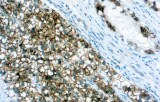

- Les études immunohistochimiques montrent systématiquement une forte expression de la PLAP dans le séminome et la néoplasie germinale intratubulaire (ITGCN), reflétant les voies de différenciation des cellules germinales sous-jacentes.

- Les profils de coloration sont généralement membranaires, avec une accentuation cytoplasmique variable, et sont souvent diffus dans le séminome, contribuant au diagnostic différentiel lorsqu’ils sont interprétés conjointement avec d’autres marqueurs des cellules germinales.

- Une forte intensité de coloration diffuse est fréquemment observée dans les échantillons de séminome et d’ITGCN, reflétant des niveaux élevés d’expression antigénique.